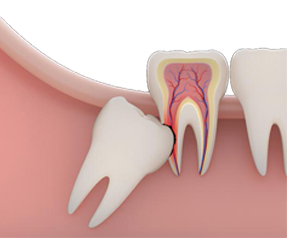

Impacted teeth